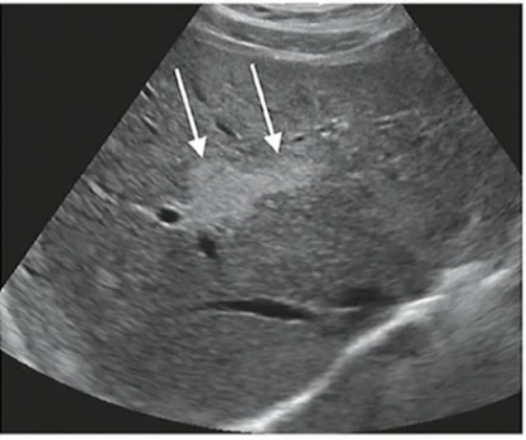

Pathology?

Fat Infiltration